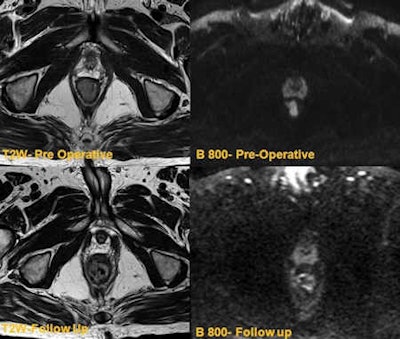

"Peri-tumor fibrosis, desmoplastic reaction, edema, inflammation occur following combined chemoradiotherapy. This poses a considerable diagnostic challenge in restaging because these post-treatment responses can produce spiculated margins and the signal characteristics resemble residual tumor on T2-weighted images. Hence overstaging is potential problem," wrote Jacob, whose co-author was Dr. Muthukumarasamy Balasubramaniam, a specialist registrar at the same institution. "DWI overcomes this pitfall as these changes do not demonstrate restricted diffusion, and the ADC values are generally high, proving to be a useful clinical tool."

Moreover, small residual tumors within the post-treatment changes can also be clearly demonstrated in DWI imaging as these tumors show high signal on high B-value due to restricted diffusion.

Patients who have responded well (complete responders) to initial chemoradiotherapy may be treated under a "wait and watch policy," and in this group of patients, DWI can be used for tumor surveillance, according to the authors. This is becoming an effective alternative for patients who do not want surgery or are not fit for a procedure. Early identification of local recurrence can be salvaged by minor endoscopic resection, avoiding major colorectal surgery.

"There have been major recent advances in focal and endoscopic techniques, with procedures such as transanal resection of tumor (TART) and transanal endoscopic micro surgery (TEMS) now becoming an increasingly common first line of treatment. However there are substantial challenges in surveillance of these patients," they noted. "Post-treatment fibrosis can often be difficult to differentiate for residual tumor on endoscopy or standard MRI. DWI can be of considerable value in follow-up of this group of patients."